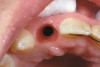

Figure 1  Replacement of a missing tooth has long been a treatment objective to improve oral health and function.

Figure 1